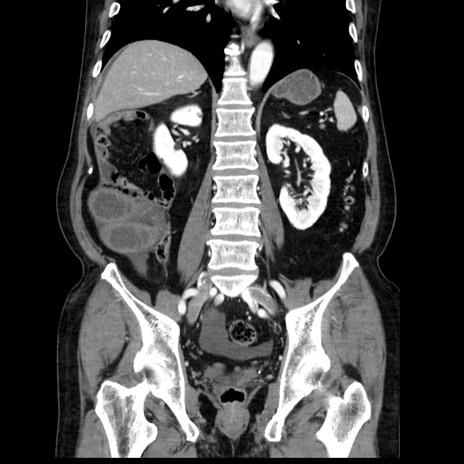

症例30(冠状断像)

【症例】80歳代男性

【主訴】臍周囲痛

【現病歴】約6時間前から臍下部痛が出現。次第に腹部膨隆・背部痛も生じてきたため来院。背部痛の場所は変化しない。

【既往歴】腎盂腎炎

【身体所見】意識清明、BT 36.3℃、BP  131/87mmHg、P 87bpm、SpO2 100%(RA)、臍周囲自発痛・圧痛あり、反跳痛なし、自発痛部位に一致して板状硬あり、腹部膨隆、腸雑音減弱、CVA tenderness両側陰性。

【データ】WBC 19600、CRP 0.33